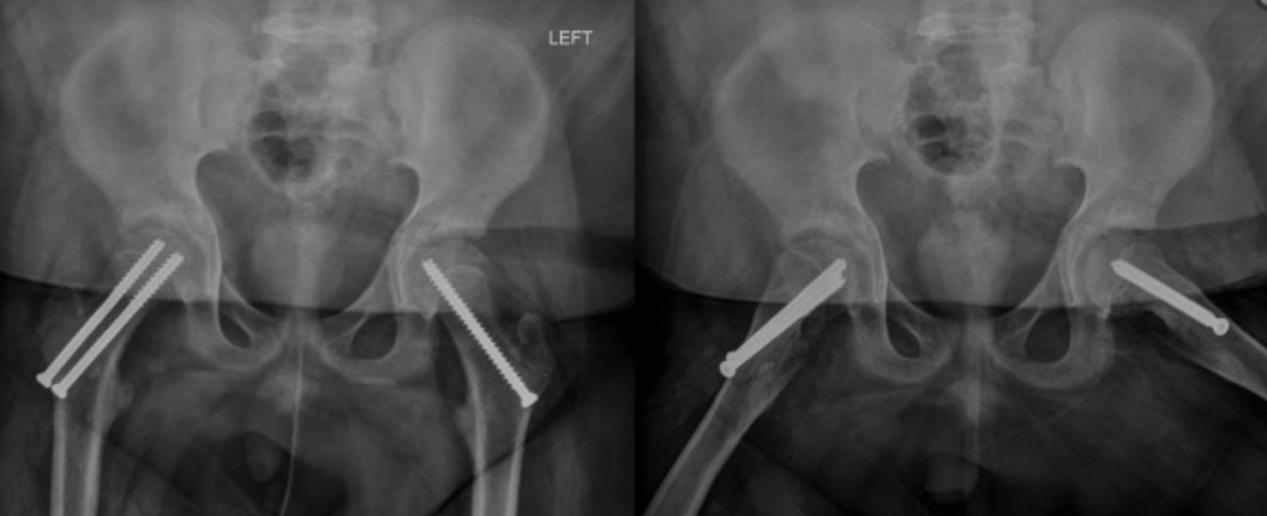

骨盆和右侧髋关节的x线片显示右侧SCFE,骺骨干角度(Southwick角)为75°(图1)。超声检查显示右侧髋关节积液(图2)。这些图像和检查证实患者目前诊断为急性严重不稳定的SCFE。病人在手术室进行了前Smith-Peterson入路,并进行了囊膜切开术,显示出有关节出血的情况。在干骺端前部轻轻按压复位。在干骺端放置两个空心螺钉以保持复位。对侧髋关节也被预防性固定非典型SCFE(图3)。

患者在6周内右侧髋关节不负重,同时在左侧保持可耐受的负重。术后8周开始独立行走。术后7个月随访,患者恢复正常,x线片未见股骨头坏死征象。双侧股骨近端的股骨仍然开放。

图3